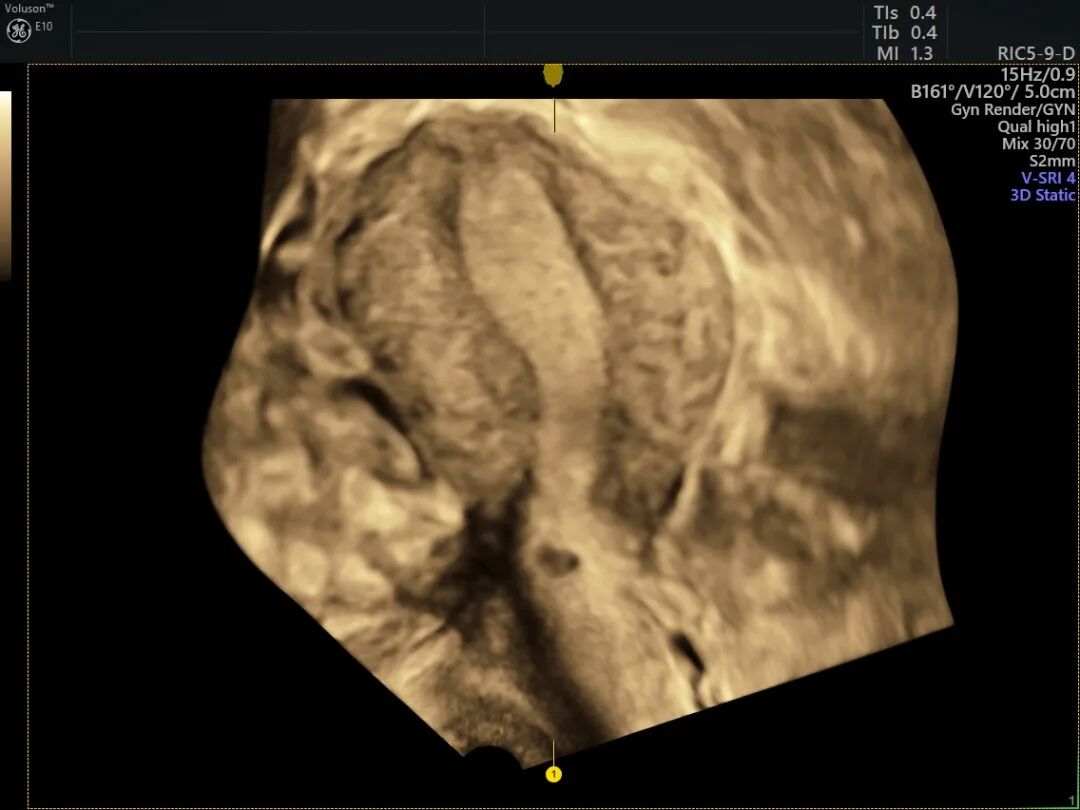

宫腔三维超声

宫腔三维可以使图像显示得栩栩如生,弥补了二维超声成像的不足,提供了丰富的立体空间信息,为疾病的诊断和治疗提供了进一步的帮助。

无创、准确性、可重复性、检查便捷。可以立体地、详尽地呈现子宫发育畸形类型、宫腔内病变位置及结构情况。

单角子宫